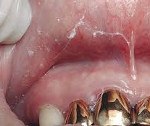

Типичная форма гальваноза проявляется наряду с повышением потенциометрических показателей более чем в 3 раза постоянными клиническими проявлениями заболевания - как местными (металлический привкус во рту, жжение, сухость, выявление при стоматологическом осмотре признаков гиперемии слизистой, явлений стоматита, гингивита, лейкоплакии ), так и общими (слабость, раздражительность, головная боль, снижение работоспособности).